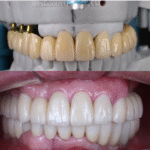

ไม่มีฟันเคี้ยว ครอบเก่าฟันหน้าไม่สวย คุณหมอบอกต้อง

ทำใหม่เกือบทั้งปาก ครอบฟัน 20 ซี่ รากเทียม 4 ซี่ ทำเสร็จแล้วคุ้มค่ามาก ยิ้มสวย ใช้งานได้ดีเลยค่ะ — คุณนิจรินทร์